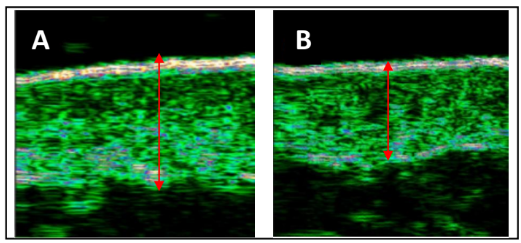

초음파 촬영을 통한 진피 치밀도 강화 확인